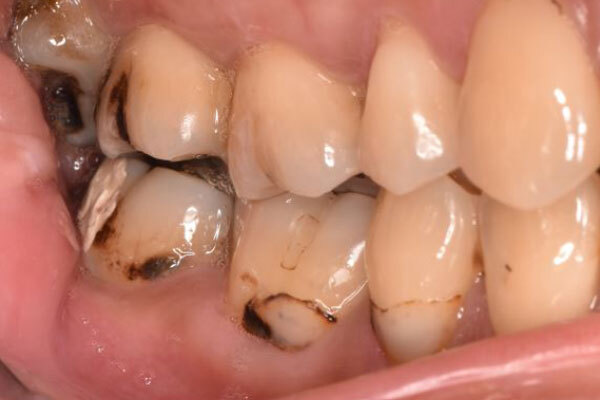

術前のデンタルX線写真と口腔内写真です。左下の一番奥の歯(#37)です。

左下の親知らずは1ヵ月ほど前に抜いたそうです。

親知らずと隣り合っていた歯の後ろ側(遠心)から虫歯が進行しています。